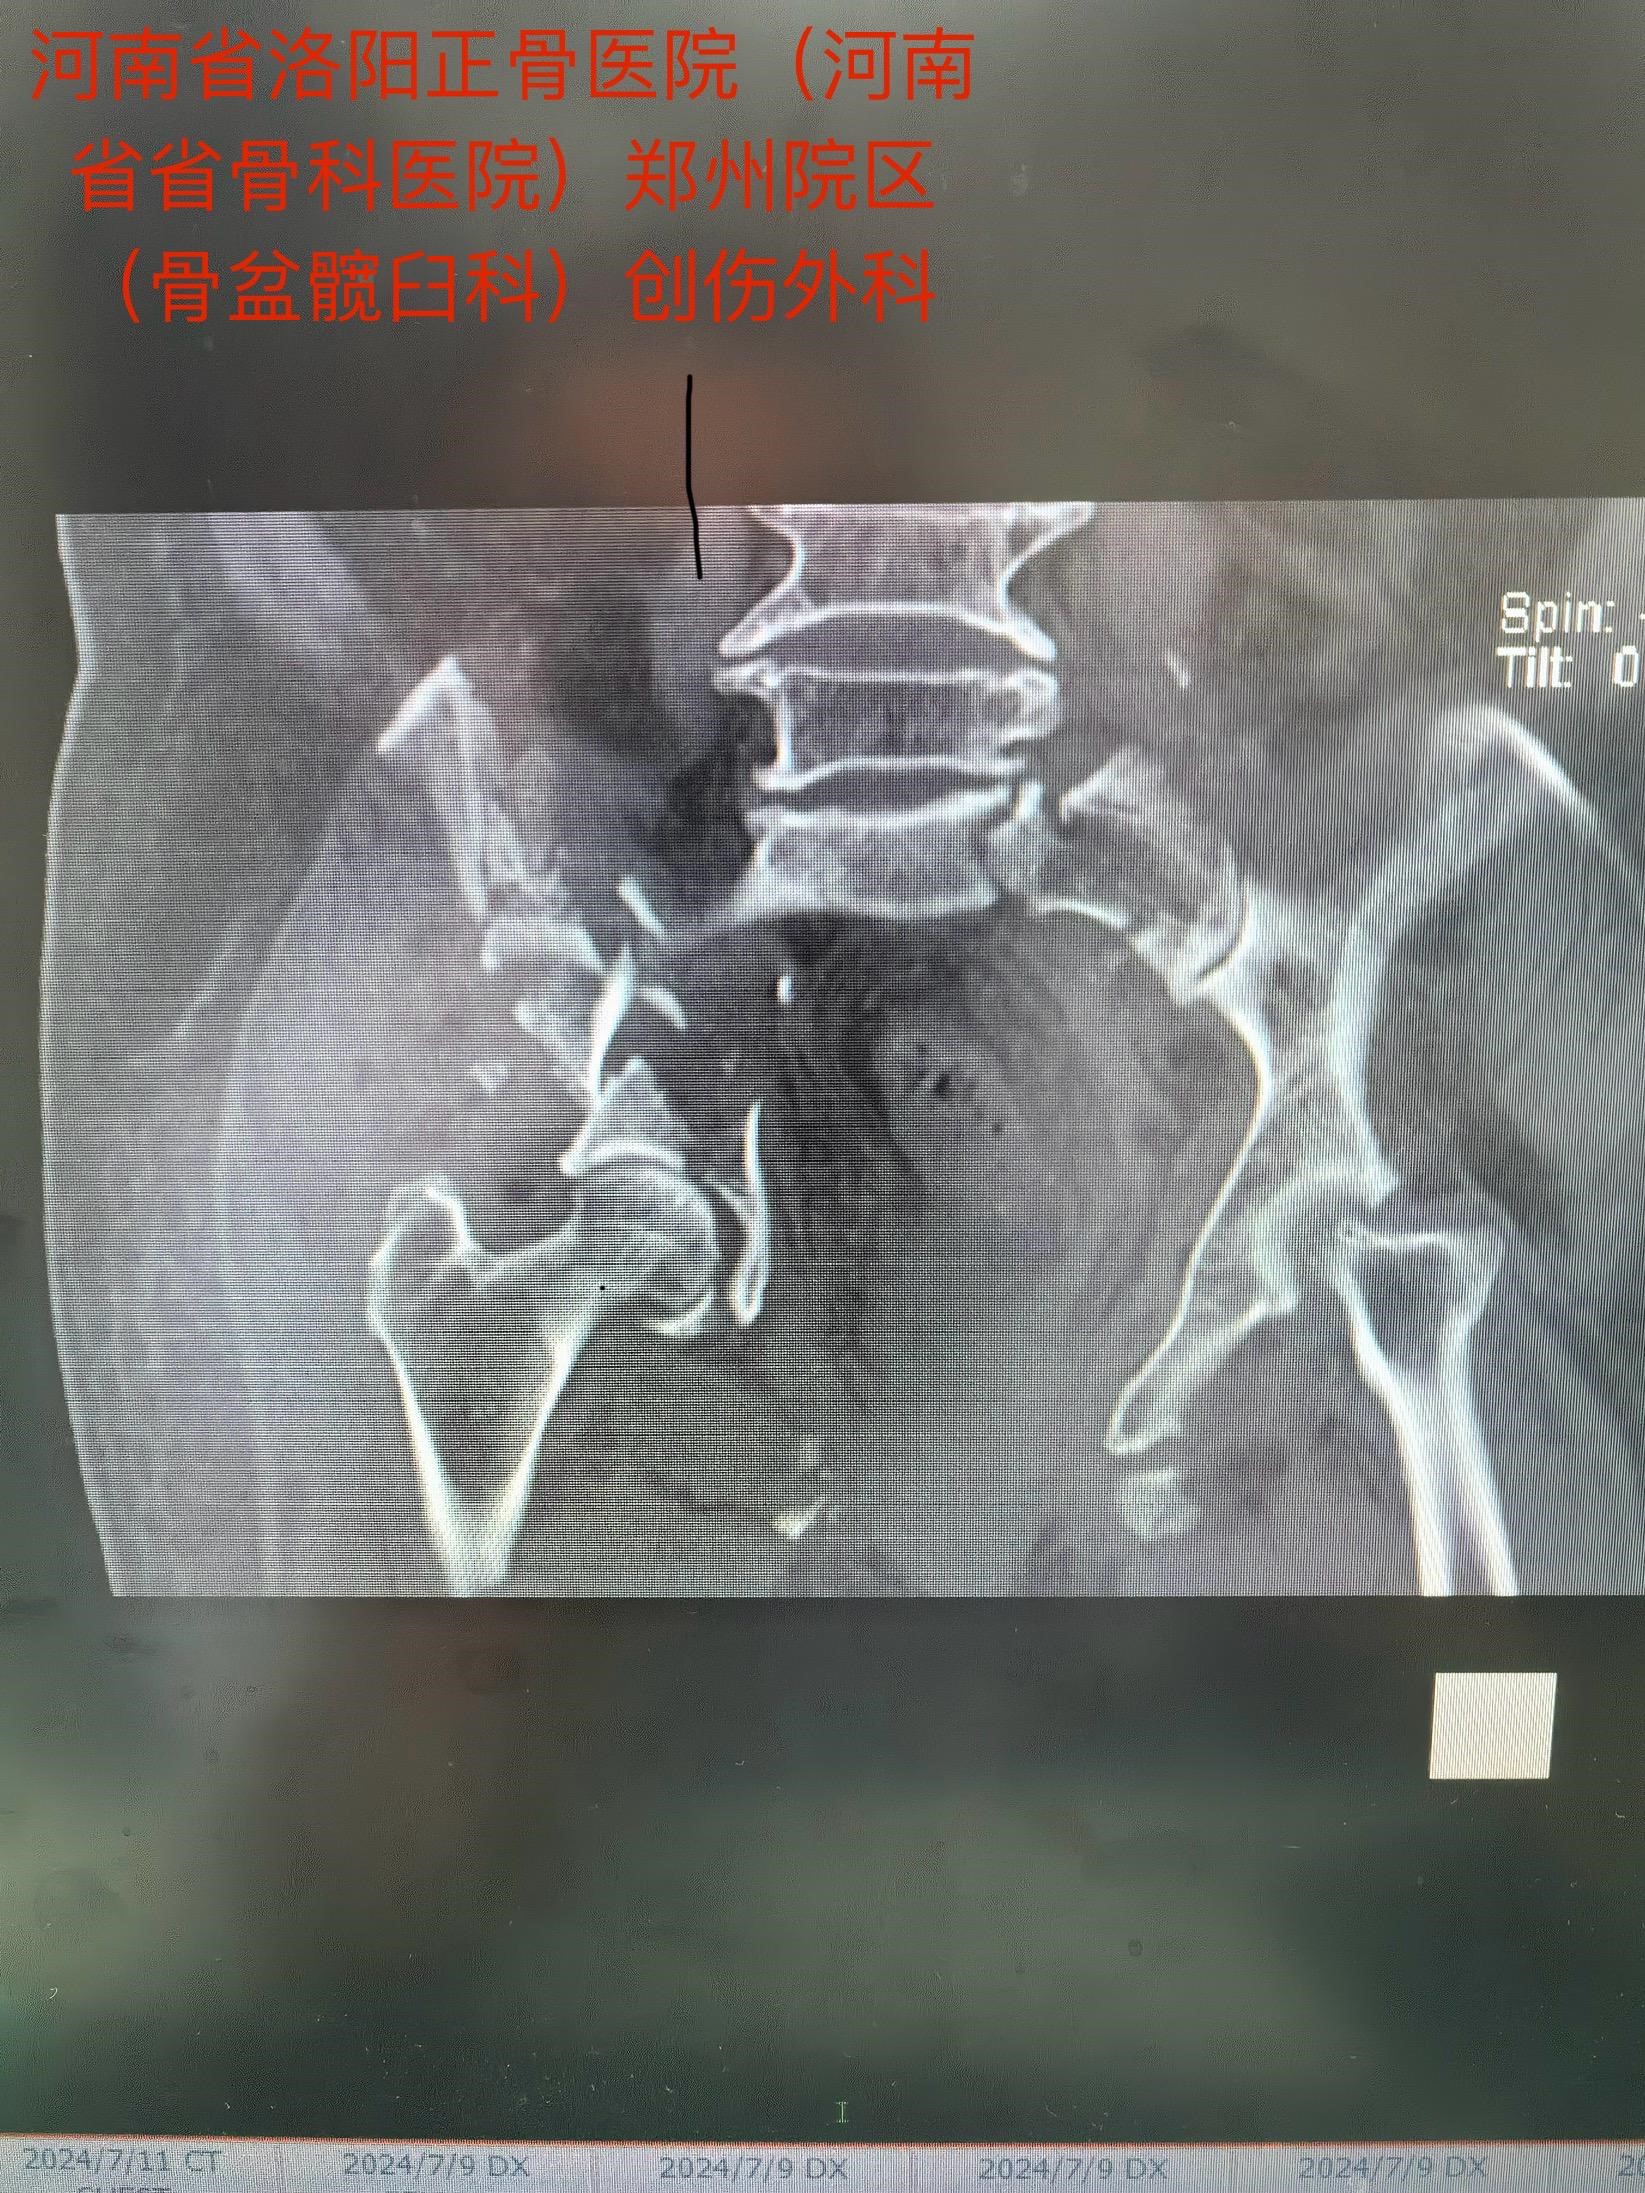

老人今年73岁,遭遇车祸后全身多处伤,在当地医院ICU治疗,生命体征平稳后,转入我院郑州院区。影像检查诊断:骨盆合并髋臼骨折,右侧髋臼双柱骨折……

马献忠主任积极倡导加速康复外科理念,对于老年骨盆髋臼骨折患者,他主张积极治疗。面对老人的复杂病情,马献忠主任积极组织多学科会诊,充分讨论,详细制定术前规划,为老人量身定制治疗方案。马献忠主任分两期进行手术:1期,右侧骨盆髋臼行单一髂腹股沟入路进行骨折复位及前后柱的固定。2期,进行左侧的微创骶髂螺钉固定骨盆后环。